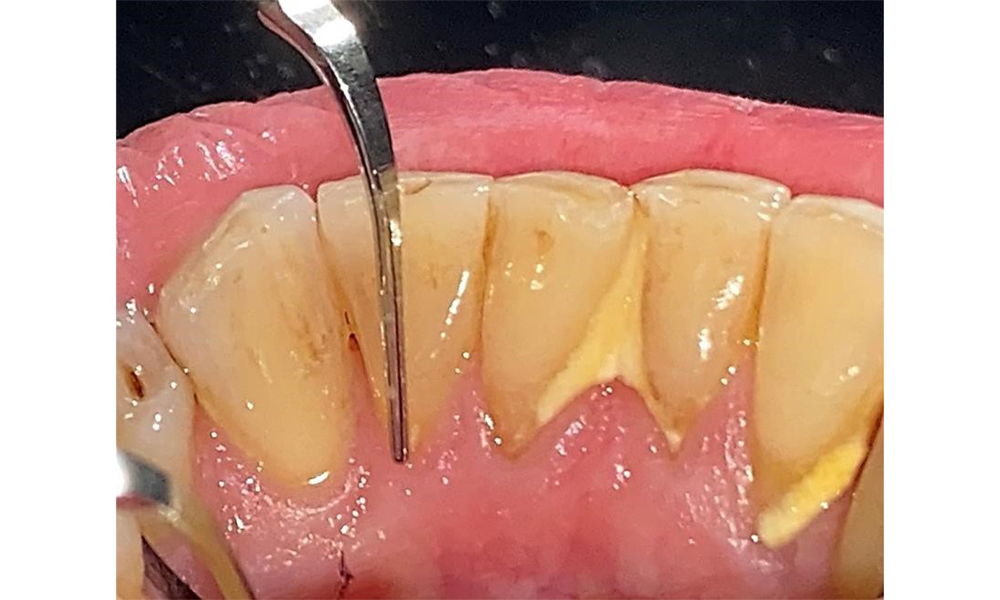

Der Patient ist ein gut eingestellter Diabetiker. Somit ergibt sich aus der Anamnese kein erhöhtes Komplikationsrisiko für die Behandlung. Grundsätzlich ist vor jeder Behandlung der HbA1c-Wert abzufragen. Die Befundaufnahme intraoral ist entscheidend für den Bedarf an dentaler und parodontaler Therapie. Aufgrund der Parodontitis ist ein parodontaler Befund mit Taschentiefensondierung und Blutungsstatus in jeder Sitzung unerlässlich (Abb. 8). Dieser gibt den individuellen Therapiebedarf vor und es kann auf eine mögliche Progression der parodontalen Vorerkrankung reagiert werden.

Sondierung für die Befundaufnahme in Rg. 27 mesiopalatinal. © Dr. R. Krapf

Abb. 8: Sondierung für die Befundaufnahme in Rg. 27 mesiopalatinal. © Dr. R. Krapf

Ein ausführlicher Parodontalstatus mit Dokumentation der Taschentiefen, Blutung auf Sondierung, Rezessionen, Furkationsbefall, Lockerungsgrad ist 1x jährlich durchzuführen. So kann rechtzeitig auf eine mögliche Progression der parodontalen Vorerkrankung reagiert werden. Die Befundung der Zahnhartsubstanz und der Wurzeloberflächen ist ebenso notwendig, da das Risiko für Wurzelkaries durch die exponierten Wurzeloberflächen steigt.